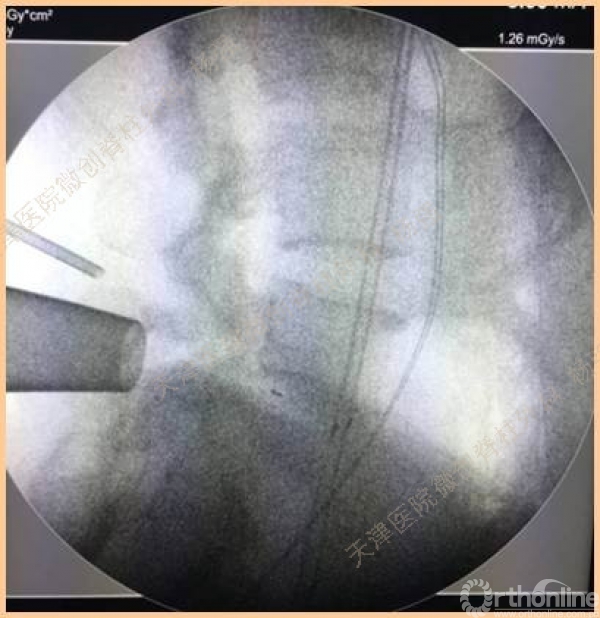

腰5椎体前滑脱I-II°,峡部裂,动力位显示腰5-骶1节段明显失稳

CT、MRI示:腰5椎体前滑脱,腰5/骶1水平间盘突出,腰5双侧椎弓峡部裂